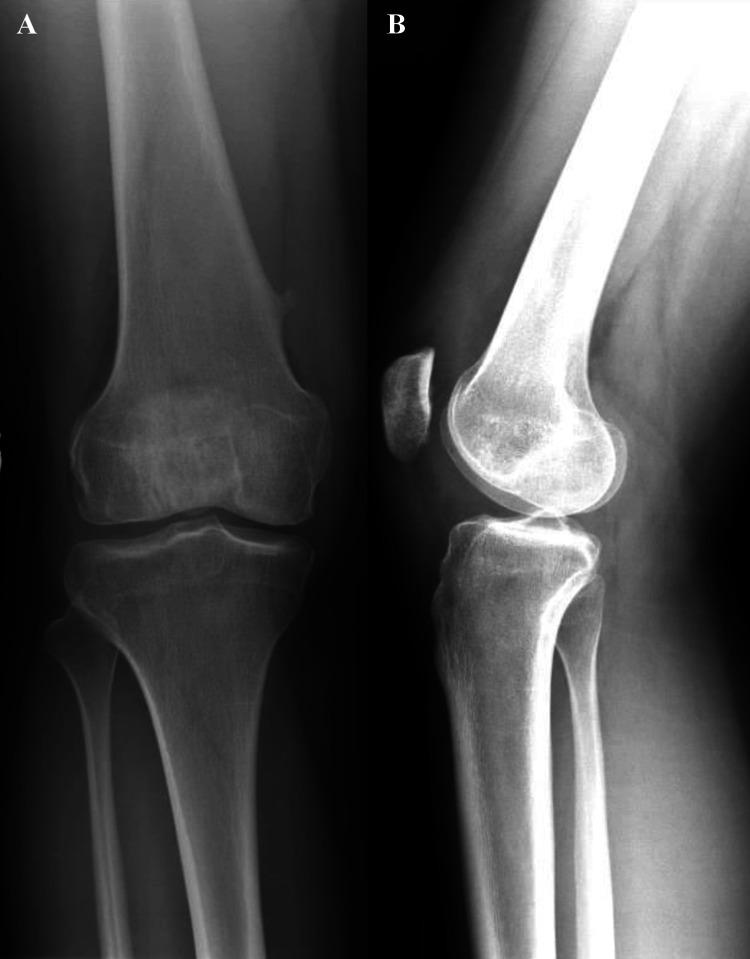

Patellar dislocation most commonly occurs laterally and is associated with underlying anatomical abnormalities such as trochlear dysplasia and patella alta. While osteochondral injuries typically involve the lateral femoral condyle, simultaneous osteochondral fractures of the medial patella and lateral femoral condyle are extremely rare and often under-diagnosed due to subtle imaging findings and spontaneous patellar reduction. The purpose of this report is to highlight a rare injury pattern following lateral patellar dislocation and to emphasize the importance of early diagnosis using advanced imaging to prevent long-term complications. This retrospective case report describes a 22-year-old female patient who presented two weeks after a lateral patellar dislocation with knee pain and limited range of motion. Diagnostic imaging, including CT and MRI, was used to evaluate the extent of injury. The patient underwent surgical intervention consisting of arthroscopic and open fixation of osteochondral fragments using K-wires and ConMed smart nails, along with retinacular release. Postoperative outcomes were monitored over an eight-month period to assess recovery, range of motion, and symptom resolution. Intraoperatively, a large osteochondral fragment was found embedded in the medial patella, matching a defect in the lateral femoral condyle. Fixation was successful. At one-week follow-up, the patient showed improvement in pain and function. By eight months, she regained full range of motion, ligamentous stability, and resolution of symptoms. Simultaneous osteochondral injury to the medial patella and lateral femoral condyle is a rare but significant complication of lateral patellar dislocation. Prompt diagnosis and surgical fixation lead to favorable outcomes.